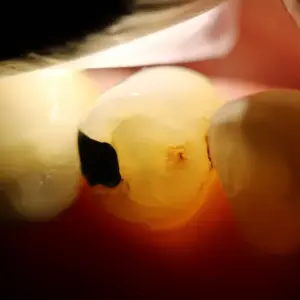

Đúng như những gì nghi vấn, tủy răng đã hoại tử. Đường gãy mở rộng xuống dưới phía xa của răng chạy tới ống tủy phía xa (Hình 5 và 6).

Hình 5 (trái) Đường nứt phía xa mở rộng.

Hình 6 (phải) Đường nứt phía xa lan tới miệng ống xa gây nên hoại tử tủy.